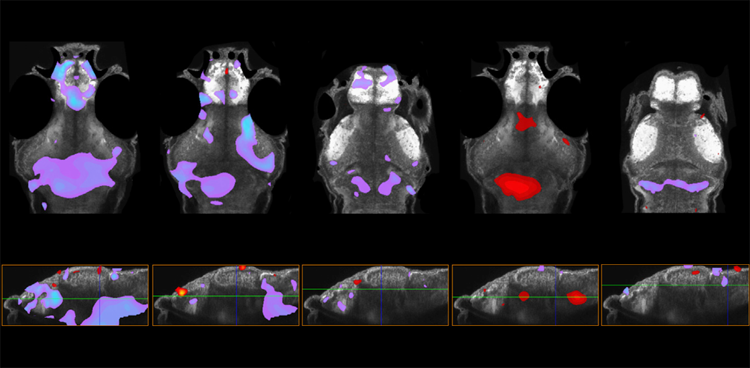

在五種具有自閉癥相關基因變異的斑馬魚模型中,前腦的大小增加(紫色)或減少(紅色)。

圖1 在五種具有自閉癥相關基因變異的斑馬魚模型中,前腦的大小增加(紫色)或減少(紅色)。